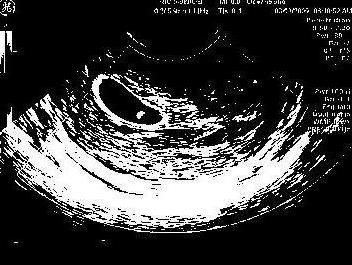

6 weeks 3/8/09

She is gorgeous Genna! Congrats!